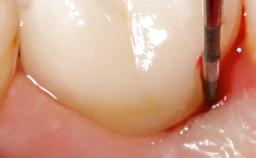

Despite anti-infective surgical treatment, some patients may experience recurrent infection and progressive bone loss requiring additional treatment. Removal of Implant Due to Recurrent Infection describes a conservative approach using an implant retrieval tool without the need for excessive bone removal or use of a trephine.

A 70-year-old female patient was referred by her general dentist to the periodontist for assessment and management of an infection associated with implant 36. The general dentist had noted suppuration on probing during examination.